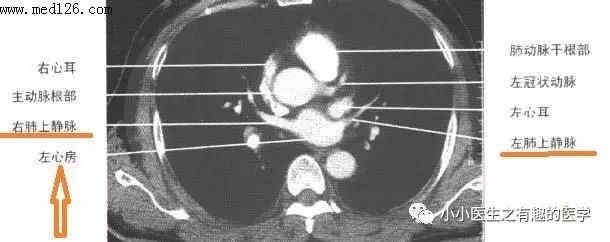

9.下面来学习一下逻辑思维。为什么下图红线标注的血管是肺静脉?因为他们和左心房相连,左心房里面流的是动脉血,而只有肺静脉里面有动脉血,所以不可能是肺动脉。

所以,基本知识很重要。